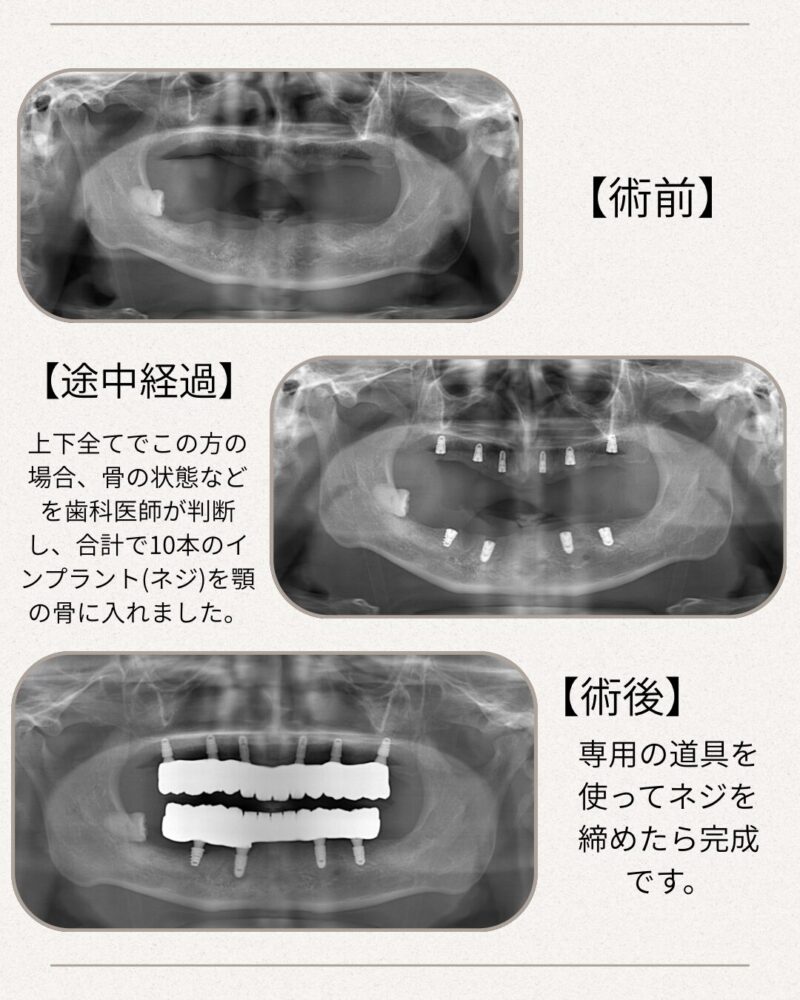

術前